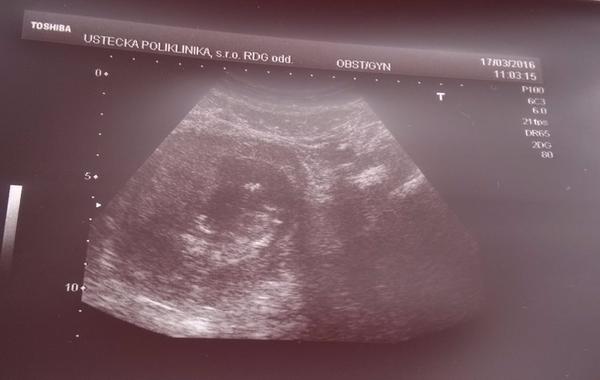

Podle UTZ mi přijde prcek malý

Jsem teď přesně ve 14tt. a na první velkém uzt jsem byla ve 12tt. Dneska jsem viděla uzt známe a ta je teď ve 13tt a měla mimi mnohem větší. Myslíte, že to může být kvalitou uzt? Když jsme na uzt s přítelem koukali, tak byl kvalitnější, než ta fotka, ale stejně se mi zdá, že je malinký, ale asi ne natolik, protože to by mě Dr. už strašila, že? 😒

Fotka z ultrazvuku vůbec neukazuje skutečnou velikost plodu. Doktor může na přístroji i přepínat mezi různými zvětšeními. Takže záleží, s jakým "zoomem" to zrovna vyfotil, to je celé (pro představu: mám fotku z 22tt a prcek na ní vypadá jen asi o půlku větší, než na té tvé fotce).

Podstatné jsou rozměry plodu, které doktor naměřil. A jelikož nepíšeš, že by to s tebou řešil, tak je zcela jistě velikost plodu v pořádku 😉